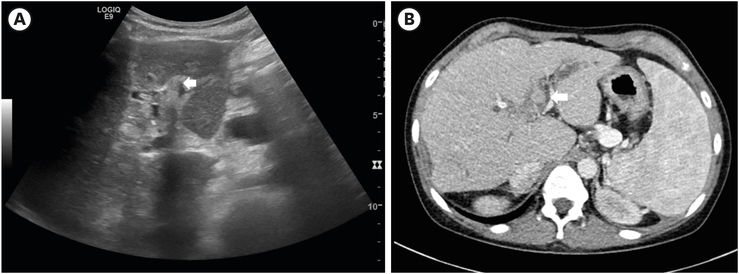

She was admitted to the pediatric department for conservative management of cholangitis and ileus. Liver ultrasonography was done on the 2nd day of admission. It revealed acute on chronic cholangiohepatitis. Echogenic material with posterior shadowing at portoenterostomy site was found in liver ultrasonography at two months prior to the ED visit. This finding was substituted by echogenic fluid at the same site (Fig. 1A). Abdominal computed tomography (CT) taken around the same time revealed stone-like material at the same location (Fig. 1B). Intravenous teicoplanin and meropenem were applied. They were also used in the previous event. However, on hospital day 9, she started to complain more severe abdominal pain. Gaseous distension in the X-ray did not improve. It seemed to be exacerbating (Fig. 2A). Abdominal CT was taken on hospital day 12. It showed long segmental dilatation of the small bowel with obstruction with a dense material that was about 3.1×3.9 cm size in the ileum. Distally migrated biliary stone was suspected for the dense material (Fig. 2B).

Fig. 2

Gallstone that induced small bowel obstruction. (A) Plain abdominal radiography revealing an obstructive small bowel ileus. (B) Computed tomogram reveling gallstone (arrow) in the small bowel. (C) A brown-colored gallstone of 3.7×3.2 cm in size found during operation.

Due to no improvement of bowel obstruction, she was transferred to the pediatric surgery department for surgical correction of gallstone ileus on hospital day 15. Laparoscopic approach was tried at first. However, open conversion via previous incision was done due to severe adhesion along the whole visceral organs. Adhesiolysis was done and a stone was removed via enterotomy at the distal ileum. It was a brown-colored gall stone of 3.7×3.2 cm in size (Fig. 2C).